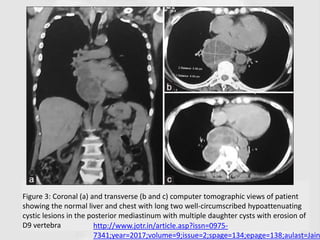

Figure 3: Coronal (a) and transverse (b and c) computer tomographic views of patient

showing the normal liver and chest with long two well-circumscribed hypoattenuating

cystic lesions in the posterior mediastinum with multiple daughter cysts with erosion of

D9 vertebra http://www.jotr.in/article.asp?issn=0975-

7341;year=2017;volume=9;issue=2;spage=134;epage=138;aulast=Jain

Figure 3: Coronal(a) and transverse (b and c) computer tomographic views of patient showing the normal liver and chest with long two well-circumscribed hypoattenuating cystic lesions in the posterior mediastinum with multiple daughter cysts with erosion of D9 vertebra http://www.jotr.in/article.asp?issn=0975- 7341;year=2017;volume=9;issue=2;spage=134;epage=138;aulast=Jain